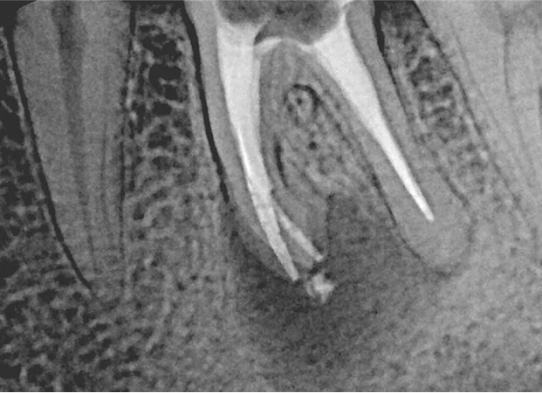

Użycie mikroskopu zabiegowego jest nieocenione, zwłaszcza przy powtórnym leczeniu. Mikroskop pozwala na precyzyjne odnajdywanie dodatkowych kanałów, które mogły zostać pominięte podczas pierwszego leczenia, a także na dokładne opracowanie systemu kanałowego. Dzięki niemu możliwe jest również usuwanie wkładów metalowych czy złamanych narzędzi.

Jednym z wyzwań w leczeniu endodontycznym jest usuwanie złamanych narzędzi z kanałów korzeniowych. To skomplikowana procedura, która wymaga ogromnego doświadczenia i zastosowania mikroskopu, ale w naszym gabinecie podejmujemy się takich wyzwań, aby uratować Twój ząb.

Na podstawie zdjęcia rentgenowskiego określa się kształt i długość kanału bądź za pomocą specjalnego urządzenia mierzy się jego długość. Potem lekarz otwiera wejścia do kanału, chroniąc ząb koferdamem, czyli specjalną gumą, zapewniającą sterylność oraz chroniącą przed środkami chemicznymi służącymi do oczyszcza-nia kanału. Używa się do tego zarówno specjalistycznego sprzętu, jak i nowo-czesnych mikroskopów, pozwalających na uzyskanie dokładnego obrazu leczone-go zęba. Ostatnią czynnością jest wypełnienie materiałem światłoutwardzal-nym i zabezpieczenie zęba przed dostaniem się i rozwojem bakterii mogących wywołać wtórny stan zapalny.

W naszym gabinecie każde leczenie kanałowe w praktyce jest przeprowadzane z użyciem mikroskopu zabiegowego. Dla nas to podstawa precyzyjnego i bezpiecznego leczenia endodontycznego. Mikroskop pozwala nam precyzyjnie uzyskać dostęp do kanałów korzeniowych przy minimalnej destrukcji zdrowych tkanek samego zęba. Widzimy więcej, więc leczymy dokładniej. Zawsze stosujemy ślinochron (koferdam), aby zapewnić sterylność i bezpieczeństwo podczas zabiegu. Używamy również nowoczesnych narzędzi maszynowych, wykonanych ze specjalnych stopów (np. NiTi), które są elastyczne i minimalizują ryzyko złamania narzędzia w kanale, nawet w przypadku zakrzywionych kanałów.